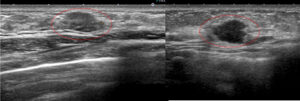

線維腺腫っぽく見えても癌 case.1

左と右(「なのは」さんのAクリニックでの初診時)比べてください。

実は左も癌です。

右の方がよっぽと「癌らしく」見えませんか?

線維腺腫っぽく見えても癌 case.2

同様に左も癌です。